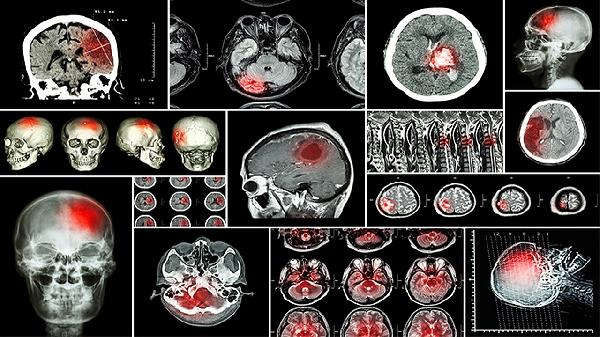

脑安滴丸主要适用于缺血性脑卒中恢复期及后遗症期出现半身不遂、肢体麻木、口舌歪斜等症状的患者,也可用于脑血管硬化、脑供血不足的辅助治疗。